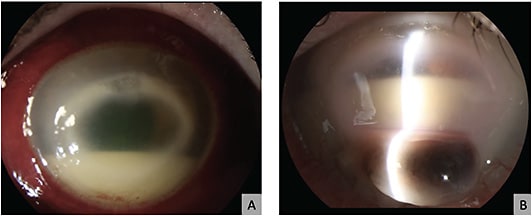

Our group reported three cases of IK treated with PACK-CXL as an adjunct treatment to standard antibiotic treatments with good long-term follow-up and results.21 We also experienced good results with another case of biopsy-proven fungal keratitis. (Figure 2, unpublished).